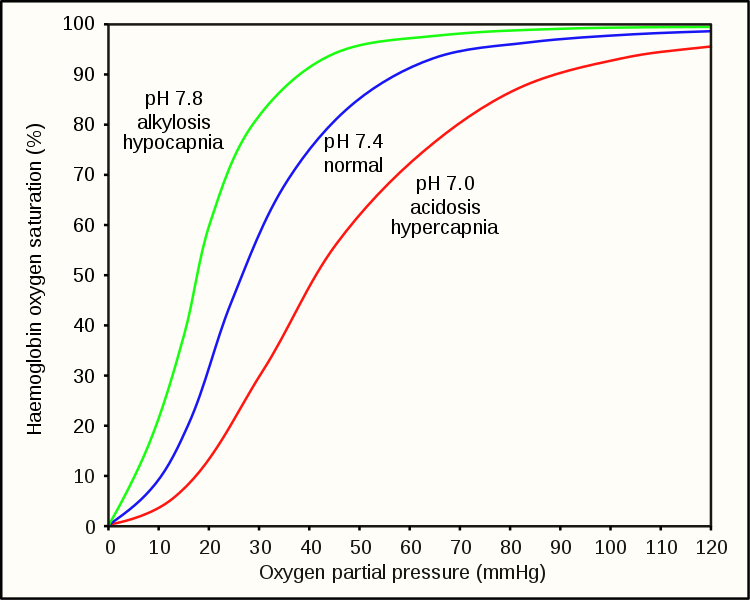

Hypoxemia – is a condition involving abnormally low blood oxygen levels. It can lead to bluish skin, difficulty breathing and fast heart rate. Apart from sleep apnea and higher altitudes, hypoxemia can be also be caused by many underlying illnesses, mainly lung and heart related especially in conditions of low environmental oxygen, diffusion impairment, hypoventilation, right -to left atrial shunting (image below).

Hypoxia – is a condition involving abnormally low levels of oxygen in body tissues. It can lead to bluish skin, confusion, difficulty breathing, restlessness and fast heart rate. Hypoxia is different to hypoxemia as hypoxia is low oxygen levels in tissues whereas hypoxemia is low oxygen levels in blood.

Hypercapnea – is also known as hypercarbia. It is a condition related to high carbon dioxide levels in the body. Carbon-dioxide can get built up in the blood if the body doesn’t successfully get rid of it within time. Conditions that either increase the levels of carbon-dioxide in the body or prevent the waste carbon-dioxide from getting to the lungs and discarded are usually the main causes of hypercapnea. Illnesses related to lung, brain, muscles and nerves are usually the most common causes. Hypercapnia is different to hypoxemia as hypercapnia is the condition with high carbon-dioxide levels in blood whereas hypoxemia is low oxygen levels in blood.